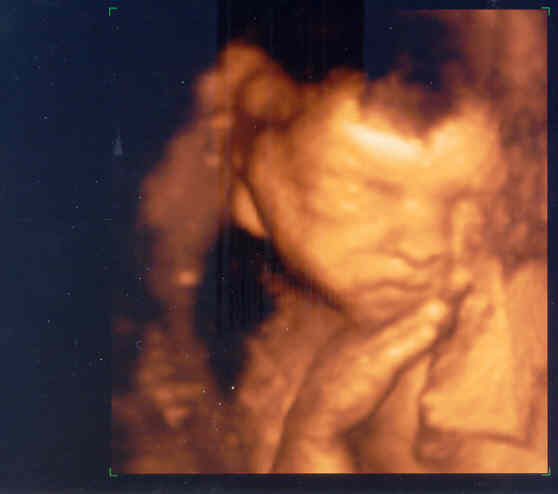

Béb nemsokára össz fog jönni nálatok is!!!!! Én mondom!!! Meg Dani is helyesel, mert akkorát rúgott belém ebben a pillanatban, hogy csak na!!!!

Jut eszembe: ne pánikoljon senki, ha 1 nap nem érzi a bébit. Bár Danit most már minden nap

(sőt napjában többször is) érzem, mert sokkal aktívabb és kevesebbet alszik, mint eddig, azért még mindig vannak napok, h éppen csak megérzem este egyszer...

Még kiszámíthatatlan...

De azt annyira jó volt követni, ahogy rájöttem, h mikor kell várnom a mozgását. PL. kaja uán mindig!

Most már délelőtt és délután is, a kezdeti esti 1-hez képest...

ÉS A LEGJOBB: Anyu volt az első, aki szombaton este érezte Danit rúgását!!!

:D:D:D:D Uram bosszankodott is, h nem ő! Kellett neki Balaton Sound-on lennie éppen akkor...